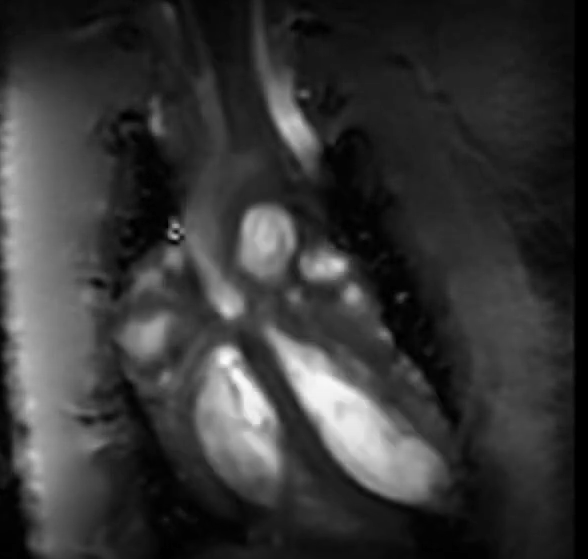

Examples of images acquired by our 7T MRI

MRI images of rat spine, brain tumor, fat imaging and mouse in-utero